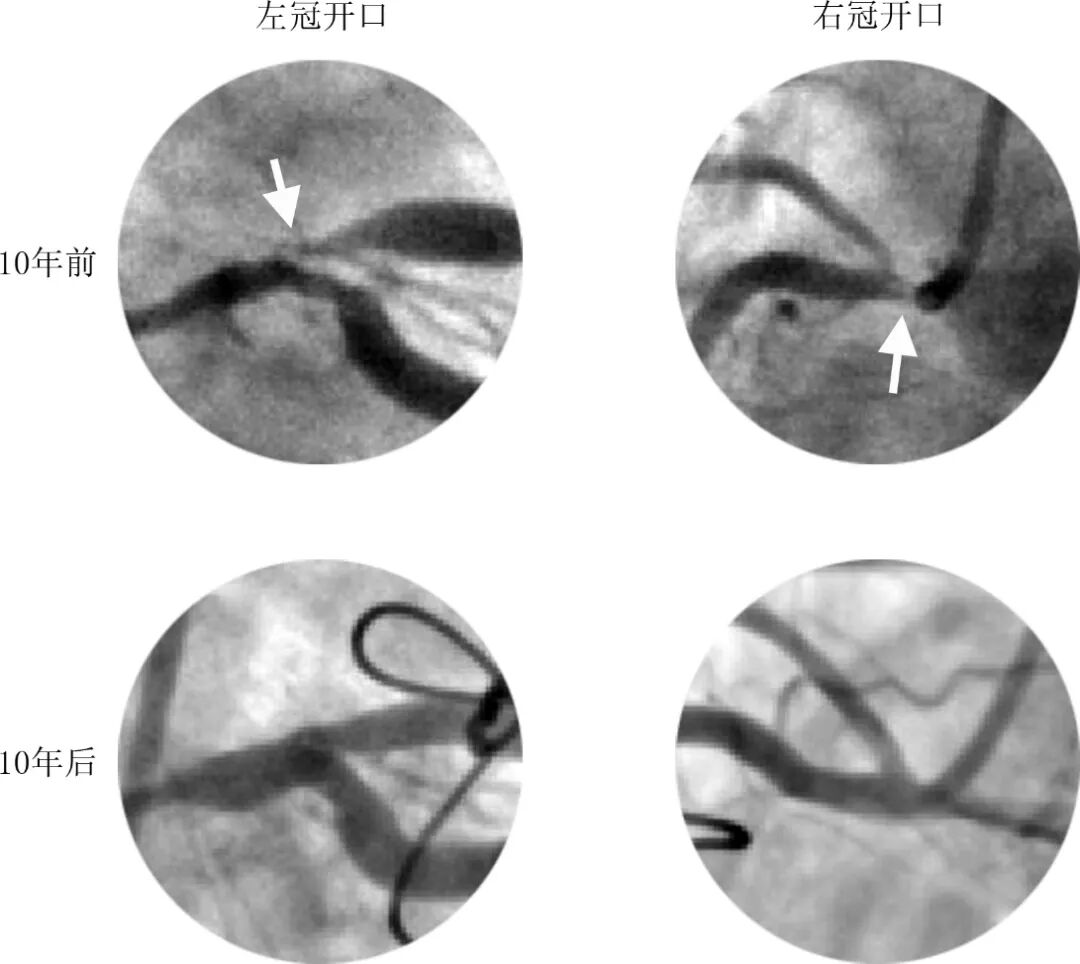

患者入导管室后血流动力学不稳定伴意识模糊,血压50/30mmHg,去甲肾上腺素微泵维持,予气管插管呼吸机辅助通气。经右股动脉植入IABP。最少造影剂、最少体位完成冠脉造影:右冠近段完全闭塞,左主干-前降支近段弥漫性狭窄95%,整个左冠系统血流缓慢(图5)。

图5冠脉造影。A 右冠,B左冠

复查造影冠脉恢复前向血流TIMI3级,整个冠脉血管显著增粗!左主干直径达5-6mm,支架植入位置为左主干-前降支近段-对角支近段(图7A),支架显著偏小。

拟开通右冠病变,SAL0.75指引导管造影到位,造影发现右冠闭塞自行缓解,管径显著性增粗,仅残余近段狭窄30%,前向血流TIMI3级(图7B)。诊断明确为冠脉痉挛!

图7 复查造影冠脉整体性增粗。A左冠,B右冠